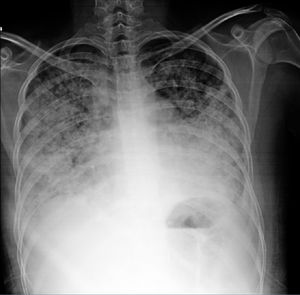

Diagnostic aspects. The differential diagnosis should include musculoskeletal pain, pulmonary embolism, infection, heart failure, uremia and neoplasm. Analysis of the pleural fluid is the main diagnostic tool. This typically is an exudate with a slight elevation of leukocytes, predomination of mononuclear cells (there are also polymorphonuclear cells) and normal or slightly low glucose levels. The differential diagnosis should include rheumatoid arthritis (RA), characterized by a higher level of leukocytes and lactate dehydrogenase, as well as a low glucose level.2 The role of the detection of antinuclear antibodies (ANA) in pleural fluid for the diagnosis of lupus pleuritis is controversial. Two recent studies17,18 have reported ANA at titers >1:160 with sensitivity of 85%–90% and specificity of 80% for the diagnosis of lupus pleuritis in patients with lupus; however, high titers can also be encountered in other conditions. Fig. 1 shows evidence of pleural effusion in a patient with lupus who reported clinical data associated with pleural involvement.

A 22-year-old woman with a 3-year history of generalized lupus erythematosus characterized by skin and musculoskeletal manifestations. She presented with a 1-month history characterized by pleuritic-like pain and dyspnea. Plain chest radiography revealed radiopaque images that obliterated the costophrenic angles, compatible with pleural effusion. It was contended with and was subsequently attributed to the activity of her underlying disease.